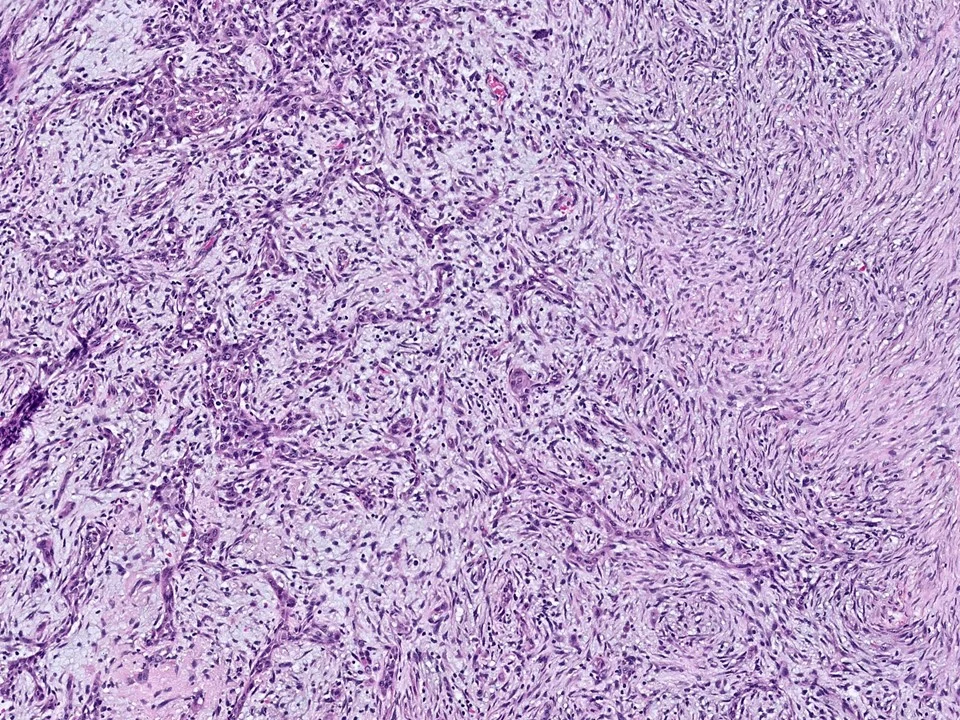

Fibromatosis

mammary fibromatosis is an infiltrative, locally aggressive proliferation of fibroblasts and myofibroblasts.

Histologically, mammary type fibromatosis is similar to desmoid-type fibromatosis in other sites. It is composed of uniform, bland spindle cells with pale eosinophilic cytoplasm, poorly defined cell borders, and oval to elongated and tapering nuclei. These cells can be seen infiltrating the stroma in long sweeping fascicles. Mitotic figures are usually not frequent. These lesions stain for beta-catenin.